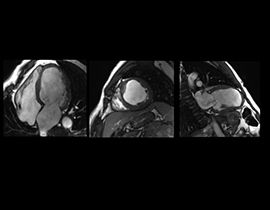

Unsere intuitiven kardialen Verfahren ermöglichen Ihnen Zugang zu Morphologie, Strömung, Funktion und Gewebevitalität sowie entscheidende Einblicke in Gefäßstrukturen und Strömungsdynamik. CVWorks ermöglicht die flexible Anpassung an verschiedene Patiententypen mit extrem vereinfachten Untersuchungs-Workflows.

Mit CVWorks können Aufnahmen mit mehrfachem Atemanhalten der Vergangenheit angehören. Unsere neuesten Single-Shot-MDE- und Black-Blood-Verfahren bieten patientenfreundliche Alternativen zum unangenehmen Luftanhalten.

Die QuickStep-Protokolle mit vereinfachtem Workflow ermöglichen Scans der Blutgefäße des gesamten Körpers in weniger als 6 Minuten. Hochleistungsgradienten ermöglichen die Darstellung von Bright-Blood-Pools und Myokardgewebekontrast mittels Cine FIESTA bei gleichbleibender räumlicher Auflösung.